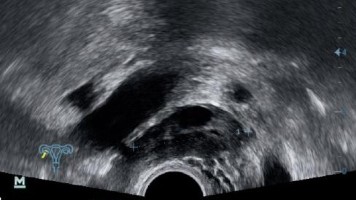

Bei einer 36-Jährigen soll bei sekundärer Sterilität eine Laparoskopie durchgeführt werden. Der Vorbefund ist scheinbar eindeutig: in der Sonographie stellt sich das Bild einer Saktosalpinx im rechten Adnexbereich dar. Doch während des Eingriffs präsentiert sich den Operierenden eine gänzlich andere Ursache.